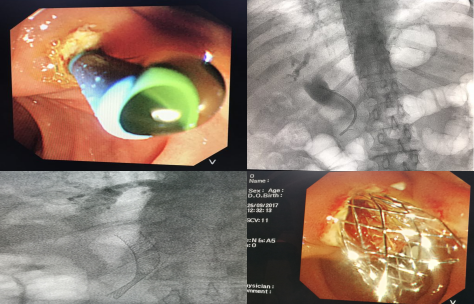

我院诊治的典型病例

病例3:胆道狭窄及胰头癌梗阻性黄疸支架置入术,手术3天患者黄疸消退。